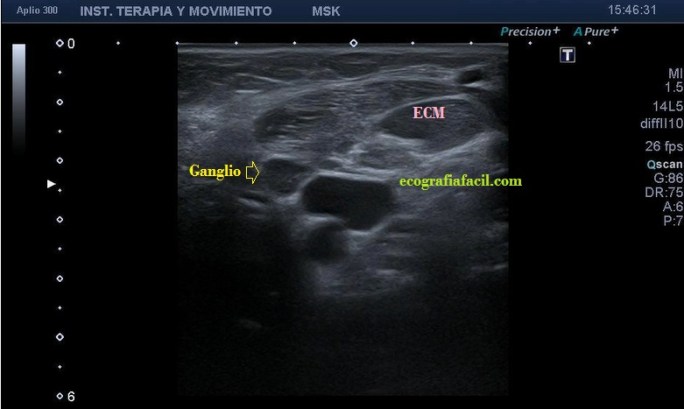

el esternocleidomastoideo, con engrosamiento del mismo y semiología heterogénea en su tercio distal. Hay ganglios locorregionales hipoecogénicos con un patrón claramente reactivo aunque mantienen su tamaño subcentimétrico (Imagen 5).

Desde la imagen 1 hasta la 4 realizadas en eje corto, el ECM está afectado claramente, pero en la imagen 7 donde ves un corte en eje largo puedes observar como el tejido celular subcutáneo también ha cambiado su aspecto y no es hipoecogénico, sino que es ligeramente hiperecogénico y que corresponde en cercanía con la afectación infecciosa del músculo, ojo a todos lo detalles (ganglios incluidos), que el árbol no nos impida ver el bosque…